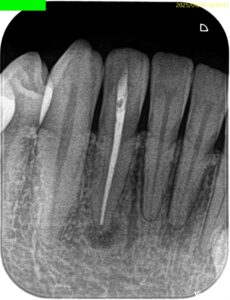

#26 RCT(2025.4.16)

緑のマジックの最下部がチャンバーオープンするべき位置であろう。

先端が細いバーで削合した。

深さは約2mmだ。

形成し、所定サイズのGutta Percha Pointで根充した。

#26 RCT 9M recall(2026.1.7)

初診時と比較した。

問題が縮小していることがわかる。

が、消失ではないのでまた半年後に見せてもらうことになった。